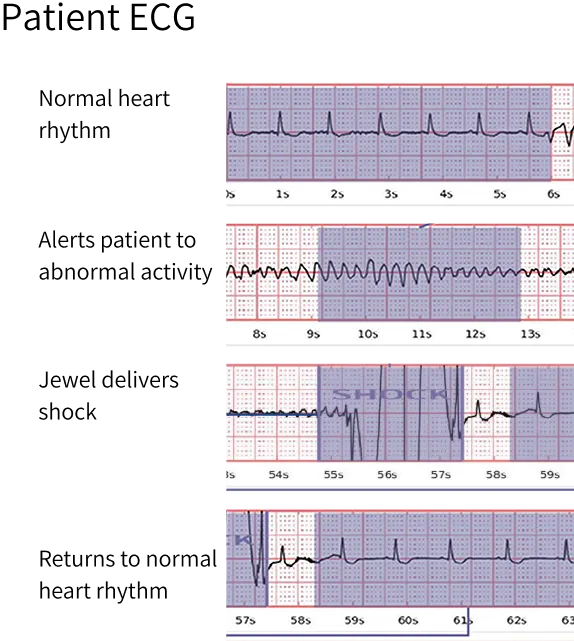

The patches are connected to the Jewel monitoring & defibrillator unit, which monitors the heart’s rhythm and can deliver life-saving therapy if needed.

The device successfully converted eight separate ventricular tachycardia or ventricular fibrillation events in six (6) different patients, effectively preventing SCA. No deaths were observed in patients while enrolled in the study.

The Jewel EP Lab Study (NCT05490459) established the foundational safety and effectiveness of Jewel to identify and convert life-threatening rhythms in a single shock.